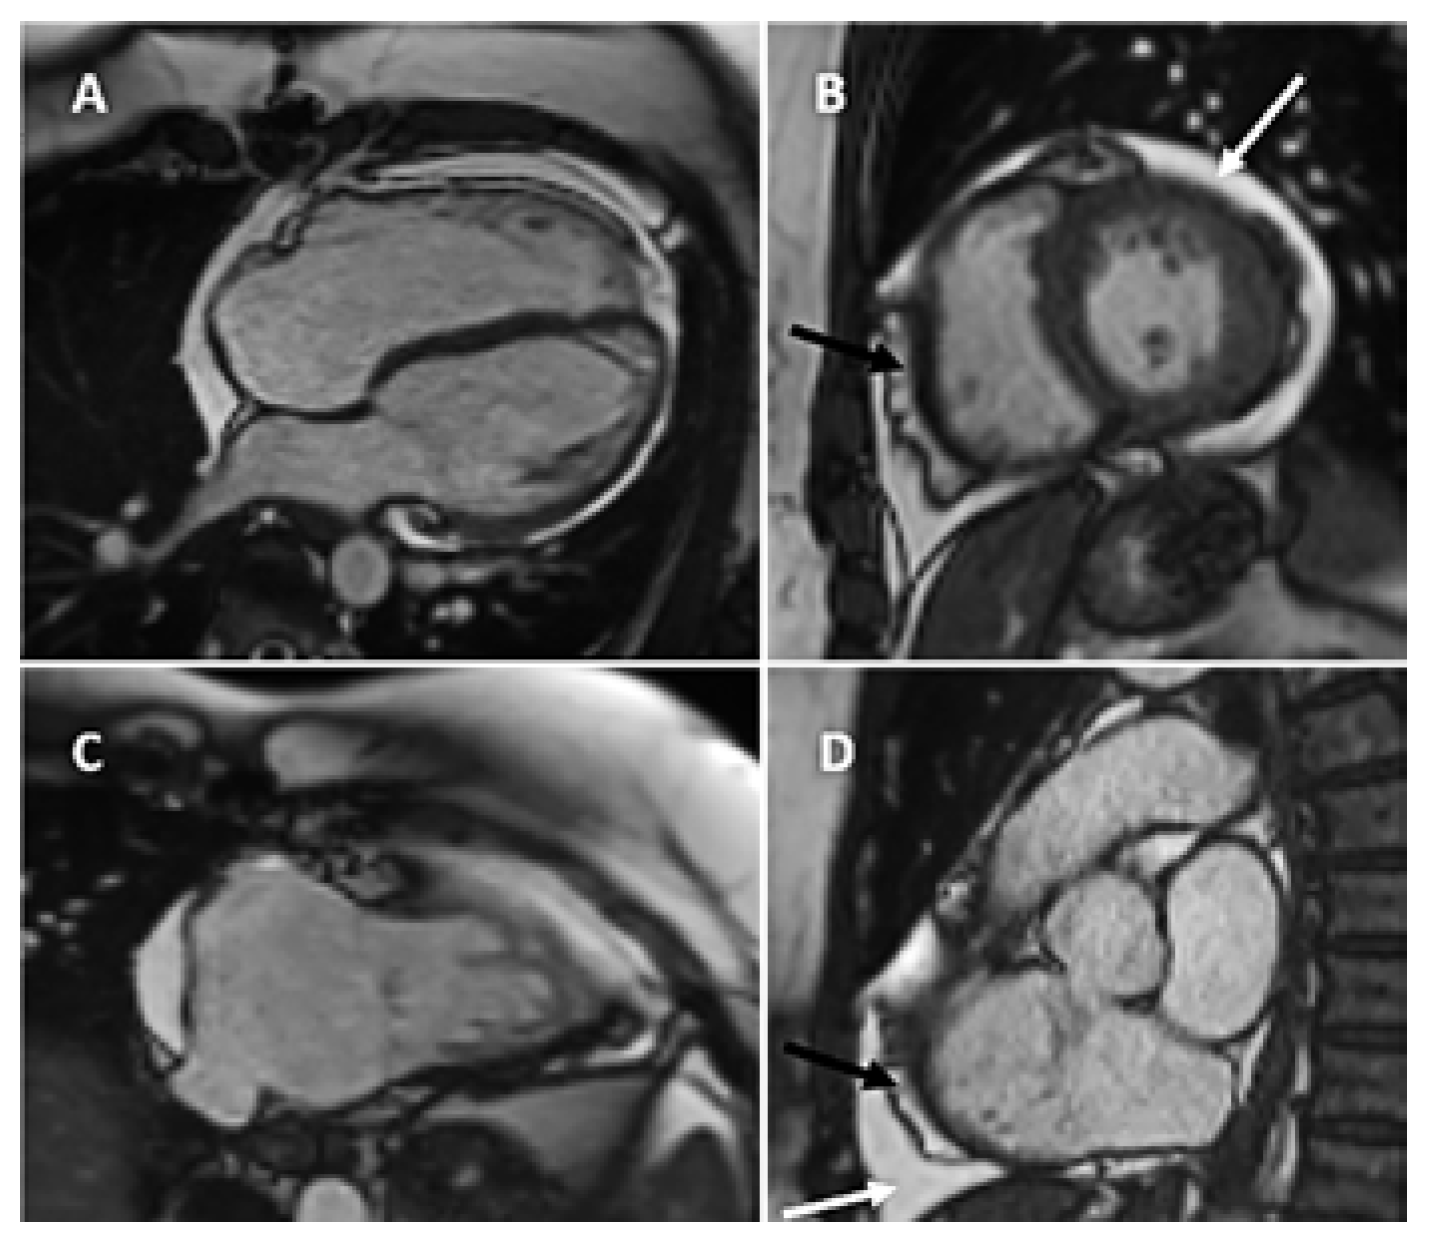

Intrapericardial Doppler Flow Signals in a Patient with Pericardial Effusion

Case Description

Discussion